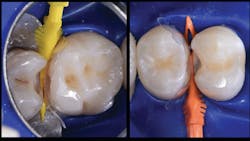

Composite resin handles more like an injectable material that tends to incorporate porosities and defects with manipulation and layering. Such defects will leave the final composite restoration prone to chips and fractures. A variation of the snowplow technique—injection of flowable composite immediately followed by injection of regular composite—can create strong, monolithic restorations; better internal adaptation to cavity preparations; reduced void formation and microleakage; and resistance to fracture.

Two key components for tight contacts are wedges and separators; in the case of the Biofit Posterior Matrix System (Bioclear Matrix), the Diamond Wedge and the Twin Ring Separator are used. It is important to use a wedge with a low profile, which provides a gingival seal without distortion of the matrix. Additionally, the separator should be able to provide strong separation and help to seal the matrix along the gingival line angles.

The final piece of the puzzle is the composite materials. In this case, Filtek One Bulk Fill Restorative (3M) and Filtek Bulk Fill Flowable Restorative (3M) were used. Bulk filling is more time efficient, technically simpler, and creates a monolithic form. Manipulation of composites and layering is known for a higher incidence of voids and defects. This case demonstrates the method of injection molding, which has the ability to create strong, monolithic, void-free, ideally contoured, mirror-finish restorations. Significant time savings occurs with simpler finishing requirements. Excess composite at the mid buccal, lingual, and occlusal areas is quickly reshaped with a disc. The subgingival area is then finished with a finishing strip. Finally, it’s time to finish and polish using a diamond-impregnated rubber polisher.